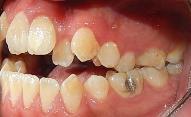

Estudios de inicio intraorales

Fotografías en la lateral derecha tenemos: relación molar clase I bilateral y relación canina clase I bilateral, líneas medias dentales coincidentes (Figura 3), -5 mm de overjet, 10% de underbite, las arcadas superior e inferior son ovaladas, apiñamiento severo superior e inferior (Figura 4).

Estudios de inicio intraorales en la fotografía de frente, tenemos la línea media dental superior se encuentra desviada a 1 mm a la izquierda y la línea media dental inferior se encuentra desviada 2 mm a la derecha (Figura 2). En la oclusal superior la forma de arco cuadrada (Figura 3). En la lateral derecha una relación molar clase II y relación canina clase II (Figura 4), izquierda una relación

molar clase II y relación canina clase II.